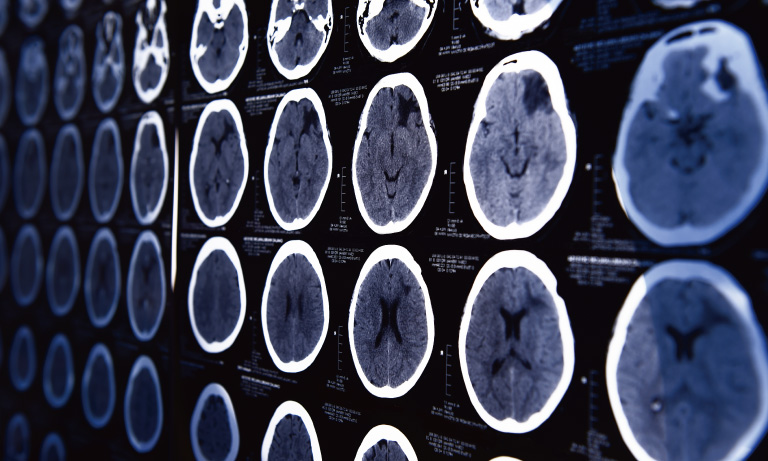

X線を利用して人体を輪切りにしたような断層画像や立体的な画像を取得して身体を検査します。浜松ホトニクスは検出器の感度向上によって、検査における低被ばく化や取得画像の高解像度化に貢献します。

PETはPositron Emission Tomography (陽電子放出断層撮影)の略です。放射性薬剤を活用して、全身の機能を検査します。がんの早期発見だけでなく、脳機能検査に使用されています。